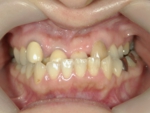

叢生(そうせい)

歯の生えるスペースが足りなかったり歯が大きいために、でこぼこに生えたり、重なって生えている状態です。乱杭歯(らんぐいば)ともいいます。犬歯が飛び出た状態の八重歯(やえば)も叢生の一種です。